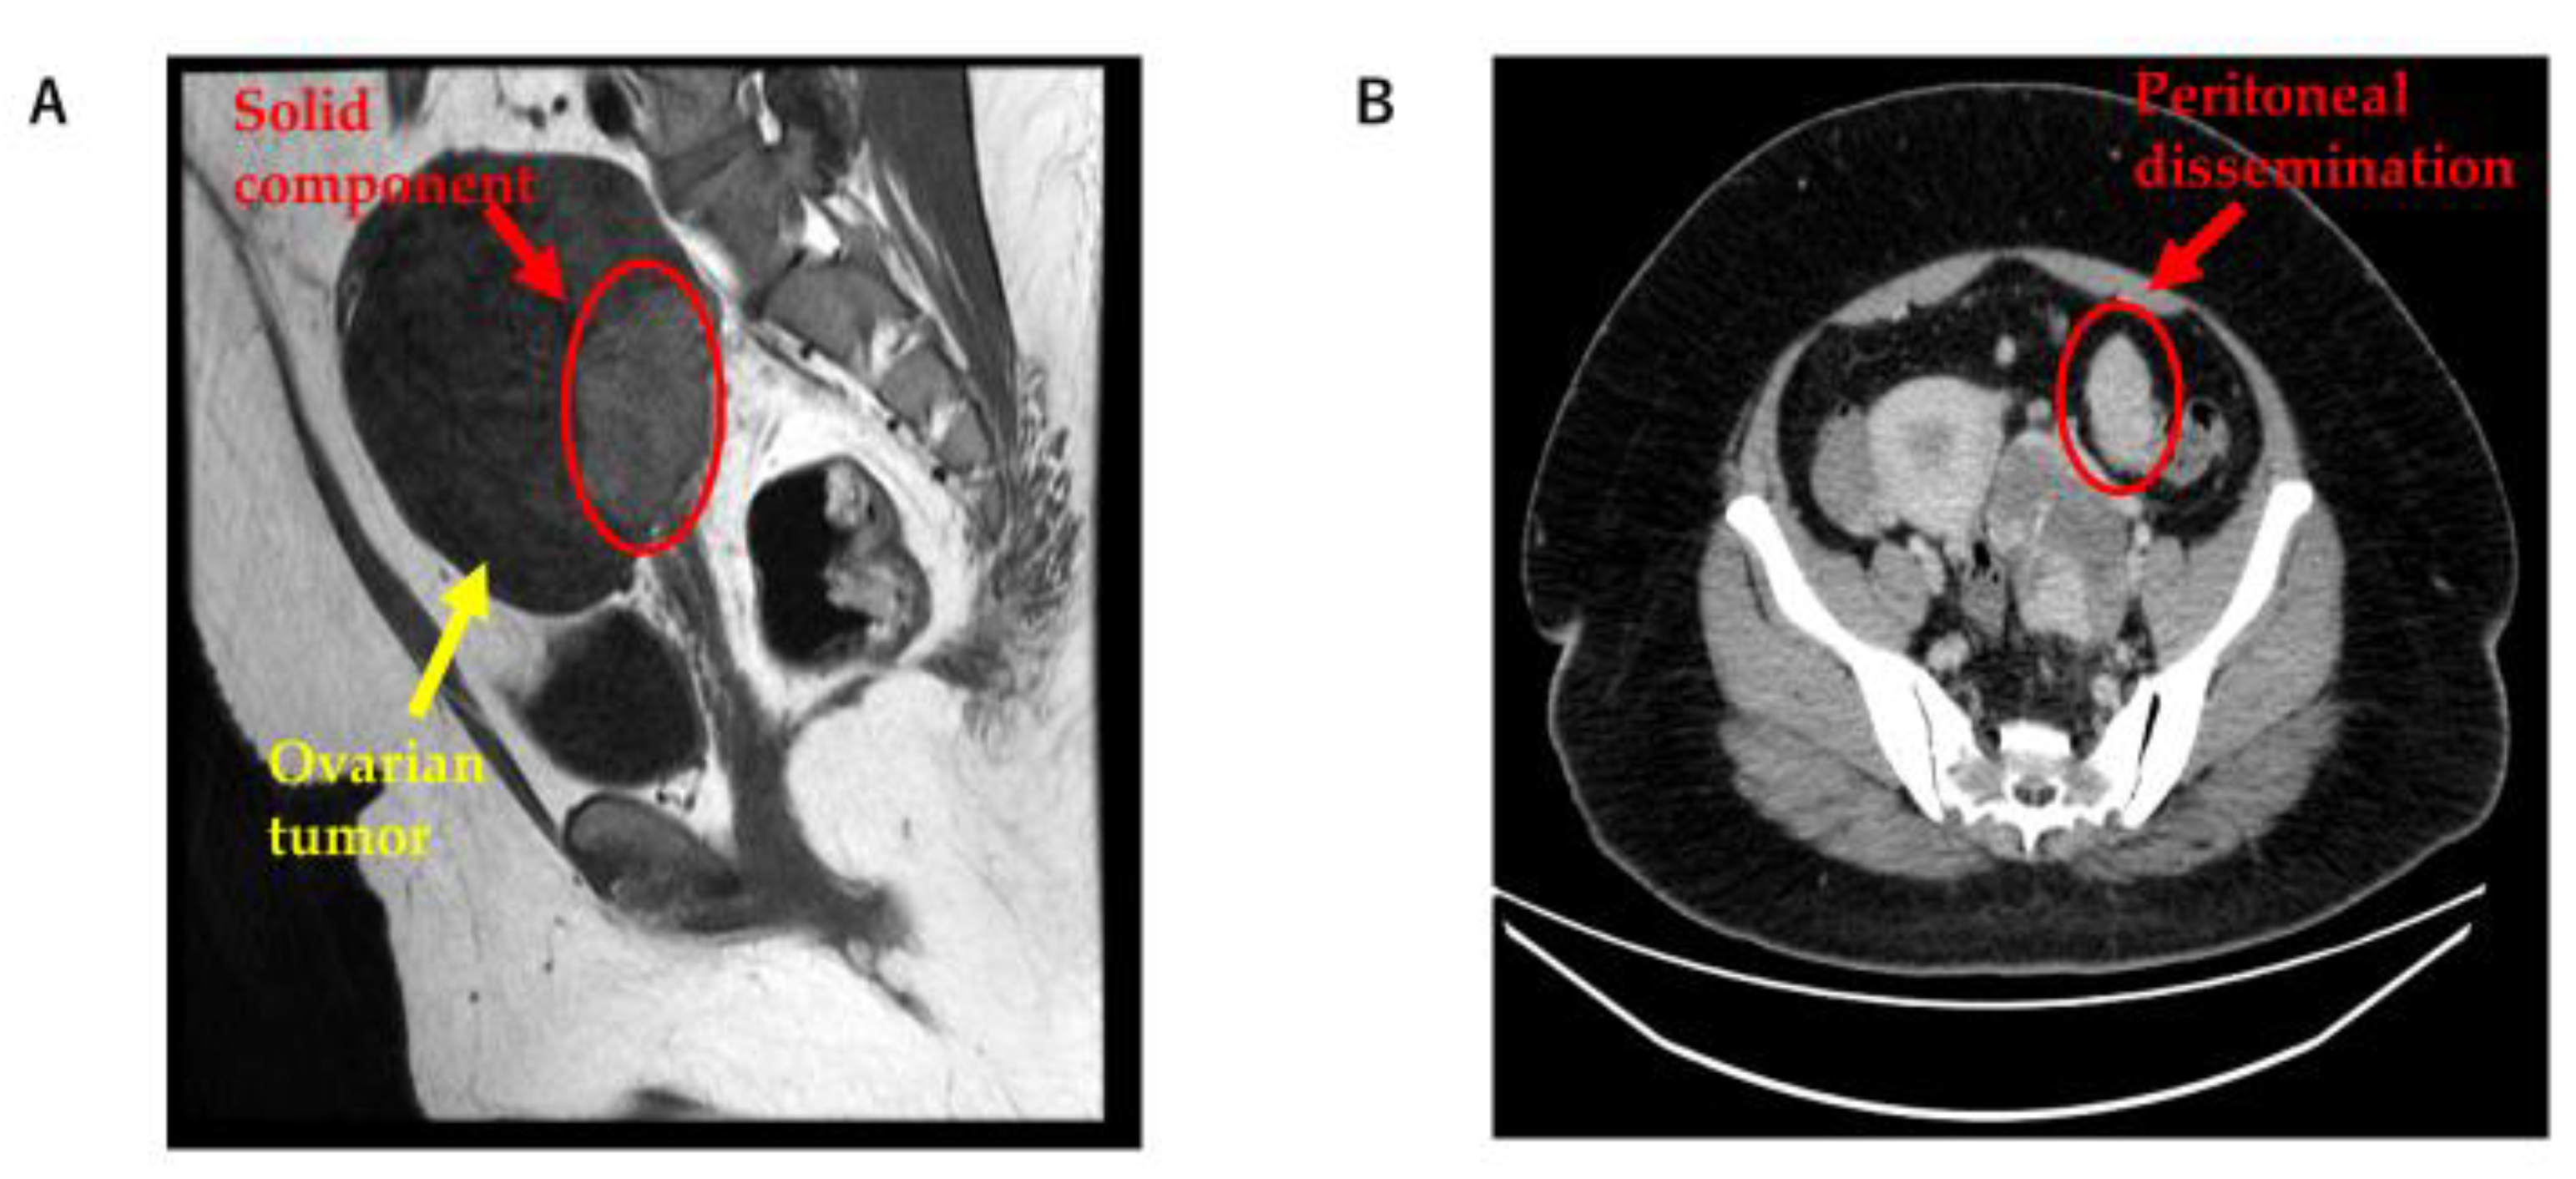

- Ukita, M.; Nakai, H.; Kotani, Y.; Tobiume, T.; Koike, E.; Tsuji, I.; Suzuki, A.; Mandai, M. Long-term survival in metastatic malignant struma ovarii treated with oral chemotherapy: A case report. Oncol. Lett. 2014, 8, 2458–2462. [Google Scholar] [CrossRef]